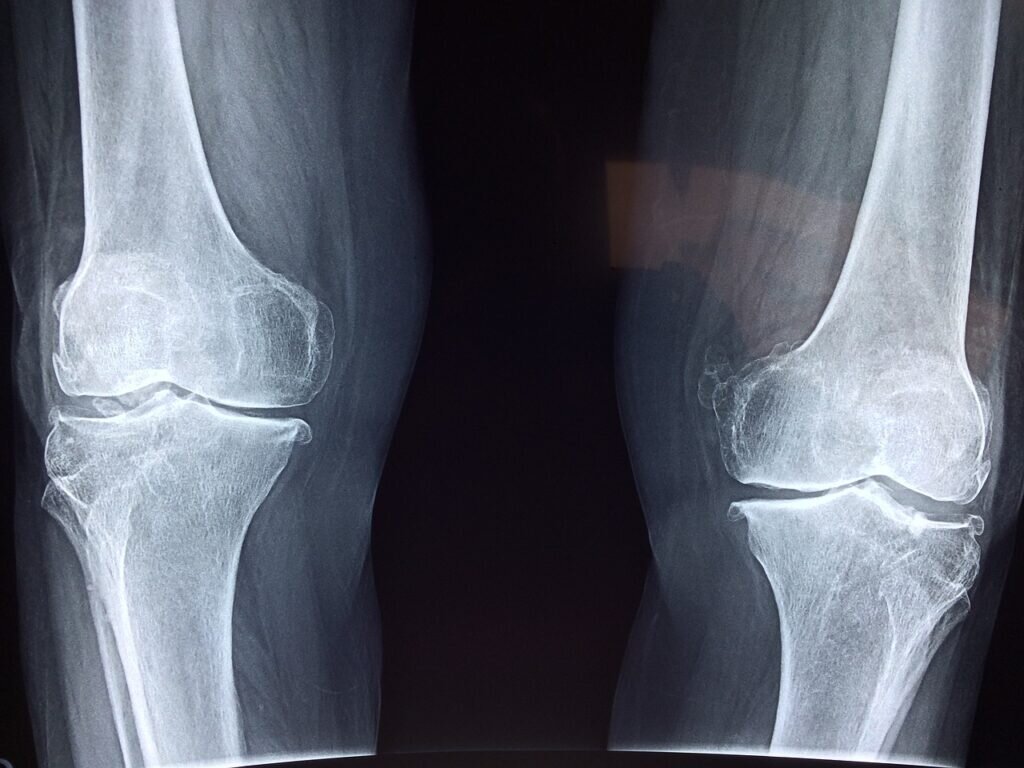

Ракова сообщила о применении роботов для эндопротезирования коленных суставов

За последние пять лет в столице в 1,5 раза было увеличено количество операций, проводимых с применением роботов нейрохирургии, урологии, онкологии и других направлениях медицины. Сейчас похожий механизм с ИИ, предназначенный для выполнения операций по тотальному эндопротезированию коленного сустава, установлен в ГКБ № 13.

Вице-мэр уточняет, что операции, которые выполняются при помощи роботической системы, отличаются исключительной точностью установки имплантатов, минимальным риском осложнений и обеспечивают максимально долгое и комфортное использование эндопротеза. Это все благодаря формированию ИИ плана операции на основании трехмерной модели сустава, которая создана с помощью компьютерной томографии. Что обеспечивает пациенту возвращение к нормальной жизни в кратчайшие сроки.

Создавая рисунок оптимальной резекции пораженных тканей, робот подготавливает суставные поверхности и костные каналы для имплантации эндопротеза коленного сустава, учитывая уникальные особенности каждого организма. При 20-минутном создании операционного плана, операция проходит в среднем за 45 минут. Нейросети также могут протестировать работоспособность эндопротеза при его установке, а у хирурга есть возможность при необходимости внести свои корректировки. Сообщает РБК.